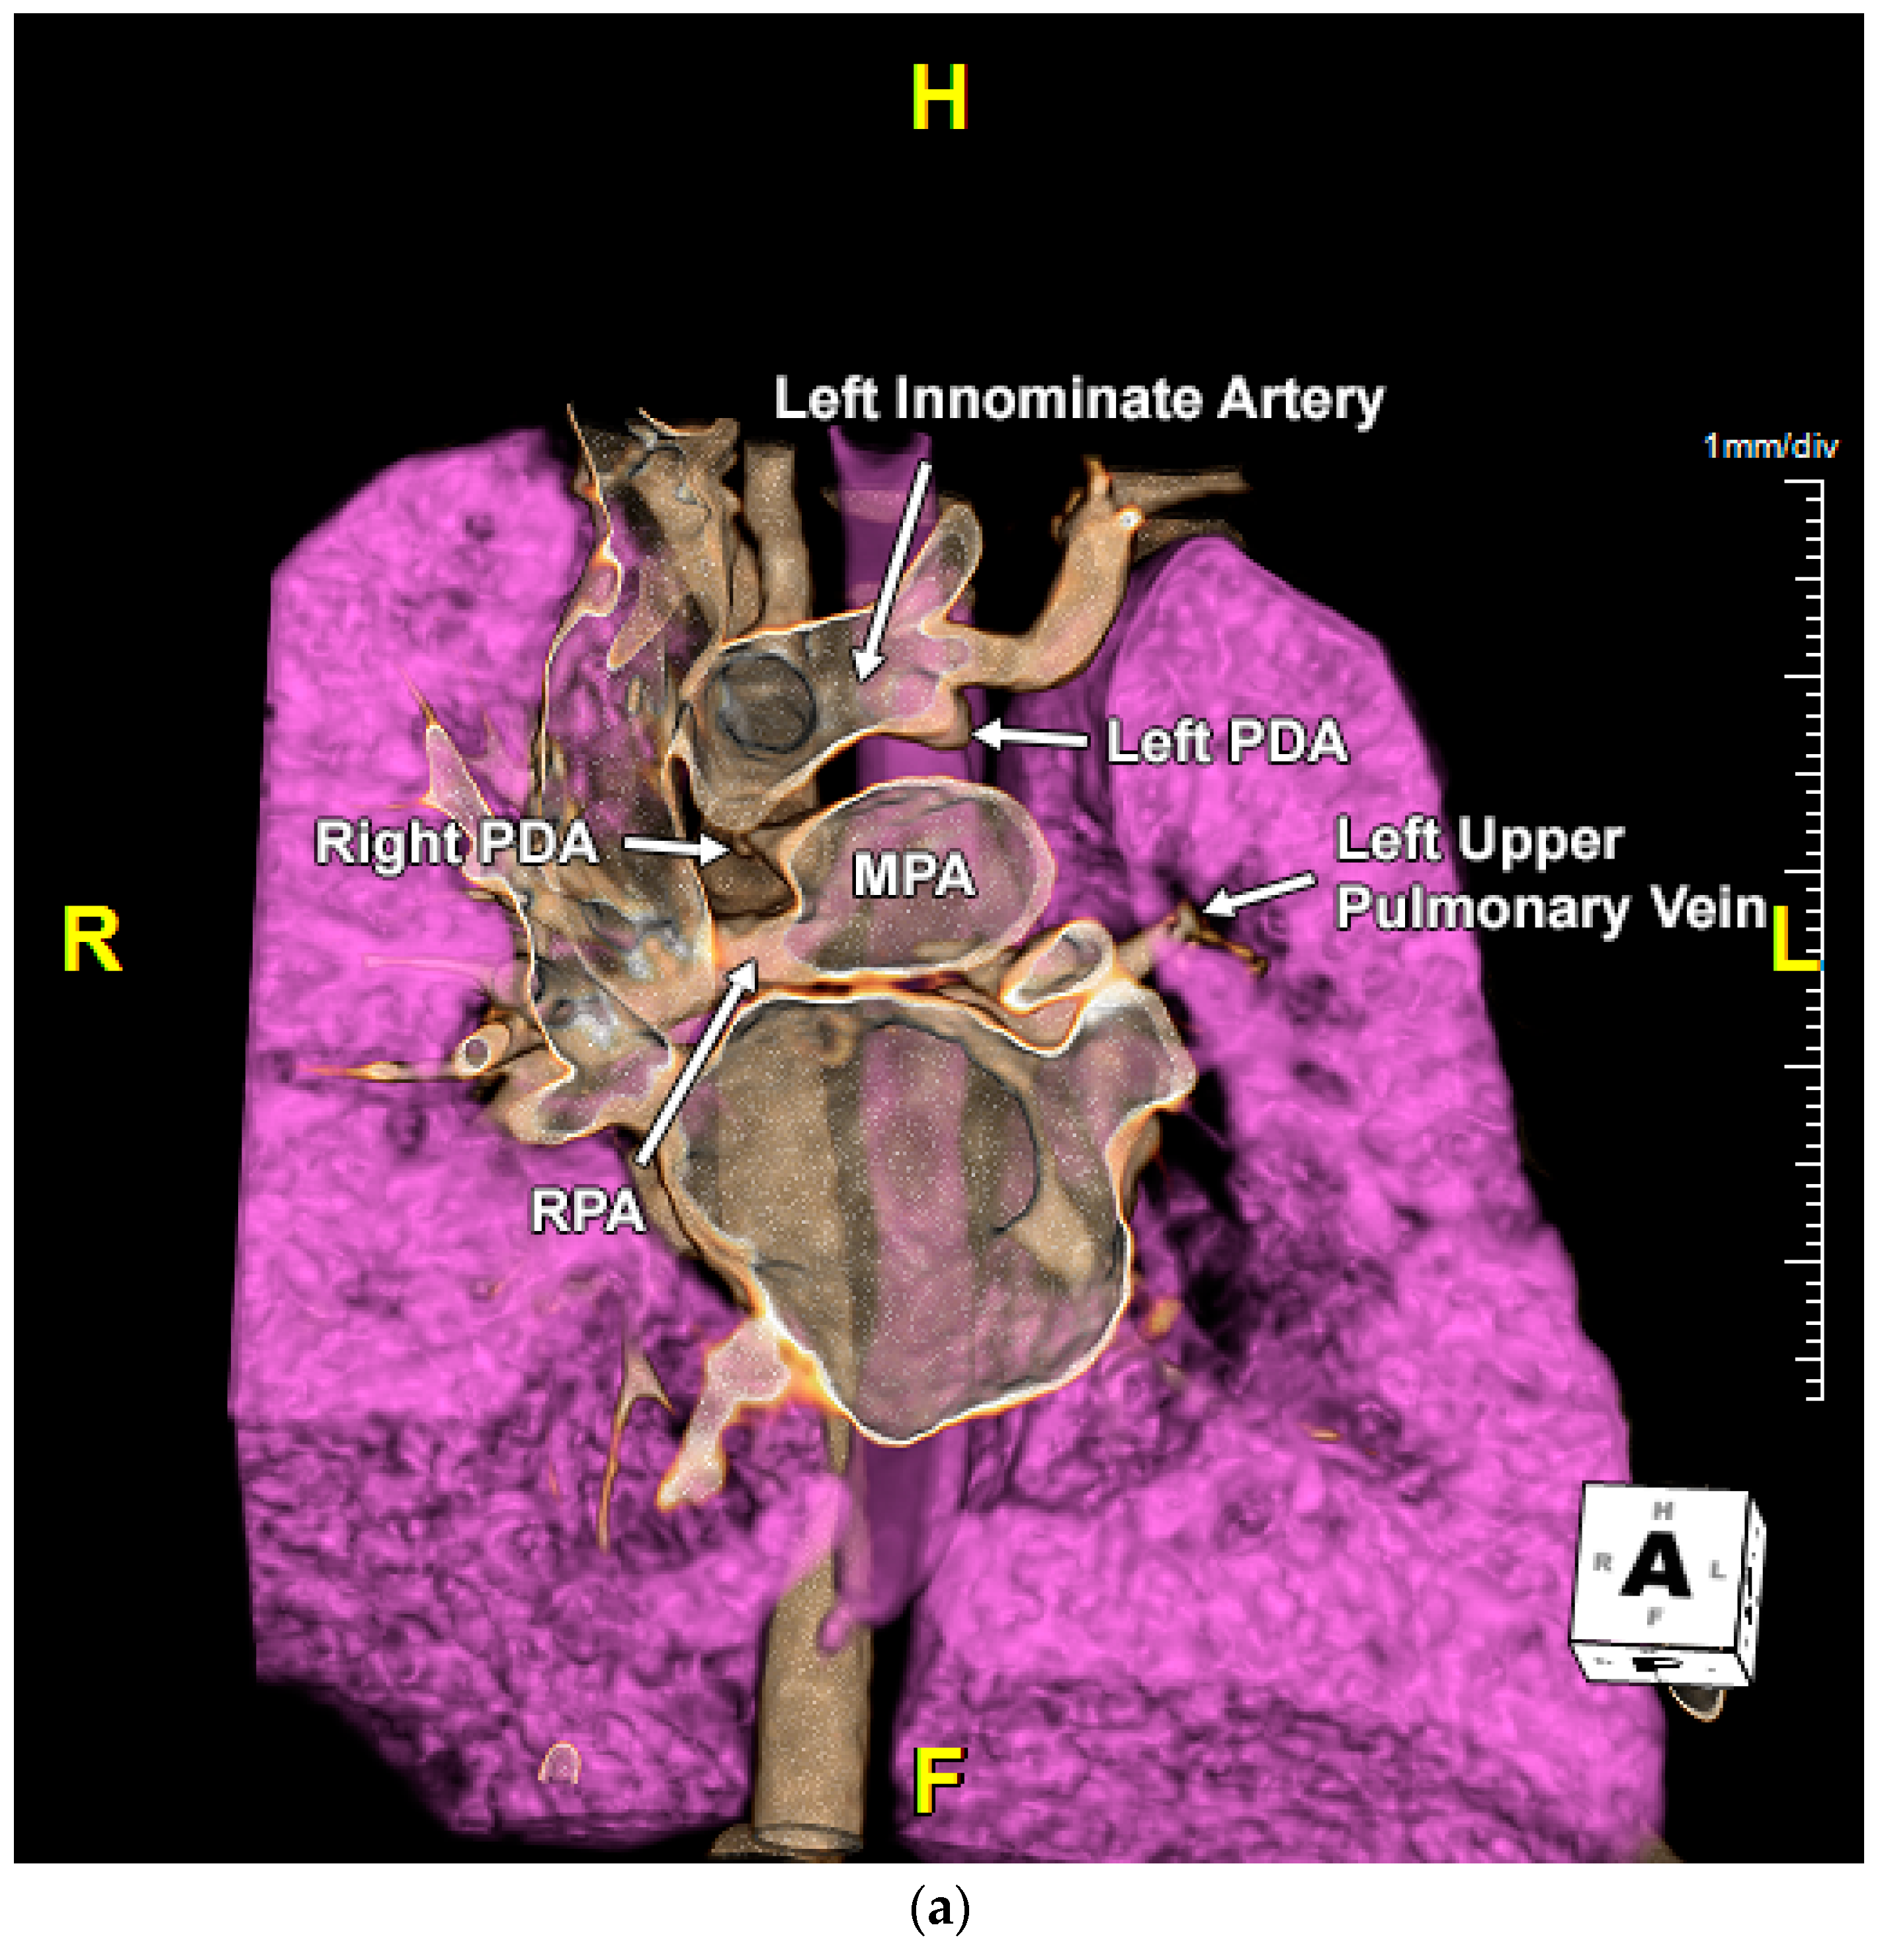

2.1. Case 1

2.2. Case 2